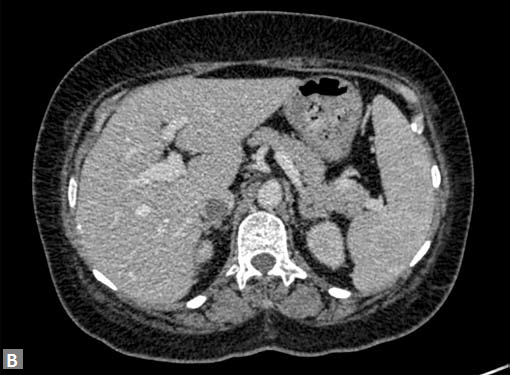

The most common mass lesion in heart is thrombus. Postinfarct clot is common in LV apex. Postinfarct aneurysm of LV may have clot. Rheumatic mitral valve disease with AF has left atrial (LA) appendage thrombus. Large one can extend to body of thrombus. Patients with arrhythmogenic right ventricular dysplasia (ARVD), sarcoidosis can have thrombus in right ventricle. SVC and IVC thrombus can extend to right atrium. Long-standing catheters can be source of thrombus in innominate veins and SVC.

Carcinomas of liver, kidney can directly extend to IVC and then into RA.

Site of the mass and prevailing clinical scenario help to differentiate the clot from neoplasm, although it may not be possible to do the same definitively.

Clots are more likely to have calcific foci (Figs 21I to K) within when they are long standing. Neoplasms with signifi cant neoangiogenesis show discernible contrast enhancement.

This phenomenon is better seen with MRI contrast than with CT contrast. Exceptionally, vascularized throm bus can show contrast enhancement.